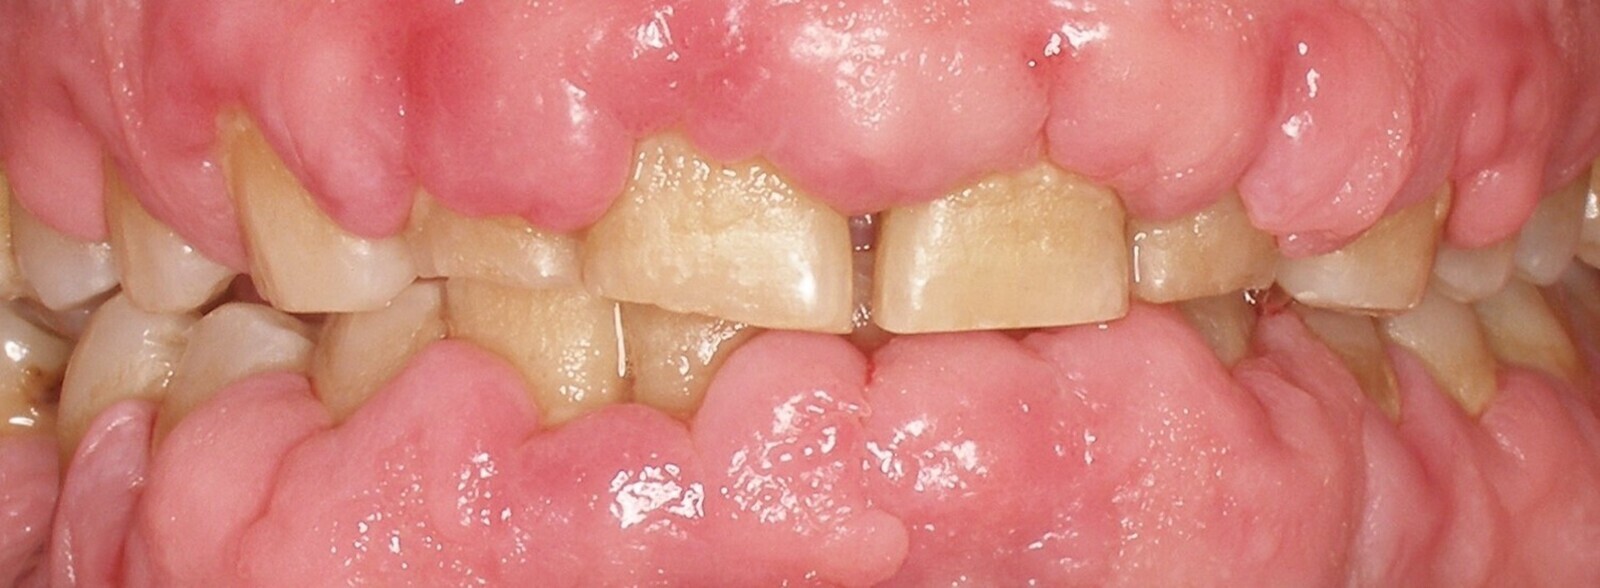

Cuando el aumento del volumen de los tejidos blandos es grande y generalizado, estos agrandamientos gingivales son medicamentosos, y es en estos casos en los que la utilización del láser presenta ventajas realmente importantes y llamativas frente a la técnica convencional (Figuras 20 y 21).

Fig. 20.

Figuras 20 y 21. Las figuras 20 y 21 indican que en los agrandamientos gingivales voluminosos, la utilización del láser presenta ventajas llamativas frente a la técnica convencional.

Mavrogiannis y colaboradores publicaron un trabajo en el que compararon tres técnicas quirúrgicas diferentes para este tratamiento y concluyeron que la cirugía de colgajo no ofreció ventajas frente a la gingivectomía convencional respecto a recurrencia y que el índice de recurrencia fue significativamente menor en pacientes tratados con láser12.